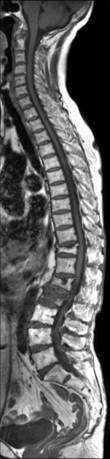

MRI検査(1台)

MRIはX線を使わずに、強い磁力と電波を利用して任意の方向の画像を描出する検査です。

当院では、3TのMRI装置が稼動しており、短時間で高画質の撮影が可能となりました。

脳外科領域においては、特に急性期の脳梗塞診断に有用であり、脊椎・関節などの整形外科領域や腹部・骨盤また、心臓領域などあらゆる部位の撮影を行っています。

脊椎画像